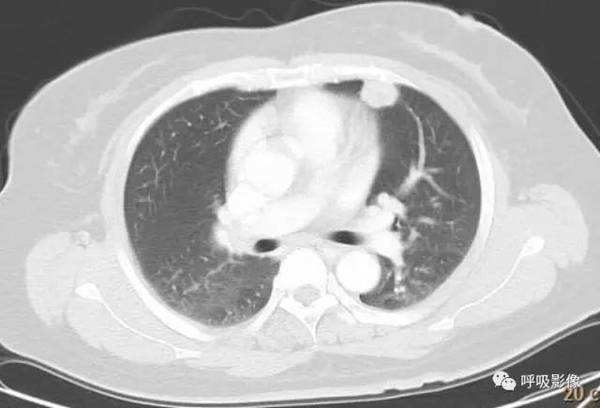

简单病史:女,35岁。查体发现肺部占位。胸部CT;右肺中叶外侧段近胸壁处圆形病变,边缘光滑,无毛刺, 增强扫描可见强化。

诊断: 肺良性肿瘤或孤立性转移瘤

诊断依据: 青年女性,右肺中叶结节影,边缘光滑,密度均匀,无明显分叶、毛刺,临近胸膜无受累、肋骨无压迹,不符合肺恶性肿瘤诊断;患者无症状,不符合感染性疾病;病变密度均匀,内无坏死,无卫星灶,不符合结核球诊断。综合考虑肺良性肿瘤或孤立性转移瘤可能性大,病变位于胸膜下,孤立性转移瘤需考虑。病变增强扫描可见血管样强化,提示原发瘤血供丰富,最终病理为绒毛膜癌肺转移。